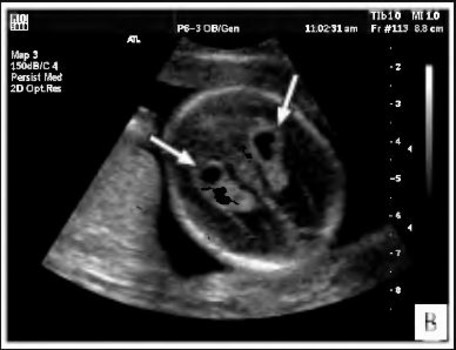

Сосудистые сплетения у плода образуются на сроке 18-19 недель. Именно в этот период, при проведении УЗИ могут быть обнаружены первые признаки кист, которые выглядят, как эхонегативные образования. Чаще всего в срок от 20 до 24 недель, когда идет активное формирование головного мозга, размер кисты уменьшается, и она полностью исчезает.

Киста сосудистого сплетения у плода до 20 недель представляет собой округлую полость, заполненную прозрачной жидкостью. При проведении скрининга капсулу обнаруживают не позднее 2 триместра. К этому периоду она обычно полностью рассасывается, когда происходит стабилизация формирования нервной системы.

Проводится в период внутриутробного формирования. Это дает возможность установить наличие кистозной опухоли на начальных этапах ее формирования.

Образование подобного полостного сплетения, расположенного в правом желудочке мозга, является односторонним. Если у ребенка есть генетические отклонения в структуре мозга, там возможны аномальные изменения. Их легко увидеть во время ультразвукового исследования.При расположении кисты в боковом сплетении наблюдается пониженное ХГЧ, что указывает на врожденную аномальную патологию.

И тогда появляется киста. Почему происходит это скопление жидкости в некоторых местах, никто из специалистов точно сказать не может. Да и разбираться в этом нет острой необходимости, потому как оно не влияет на здоровье малыша. Эти скопления при ультразвуковом исследовании похожи на кисту, потому их так и обозначают в заключениях.

По неизвестным до сих пор причинам у некоторых эмбрионов возникает так называемая киста сосудистого сплетения головного мозга у плода. По факту это скопление жидкости в самом сплетении, которое выглядит на УЗИ как киста. Оно встречается с частотой от 1 до 3% всех случаев обследования беременных, иногда киста может быть односторонней или двусторонней, единичной или множественной.